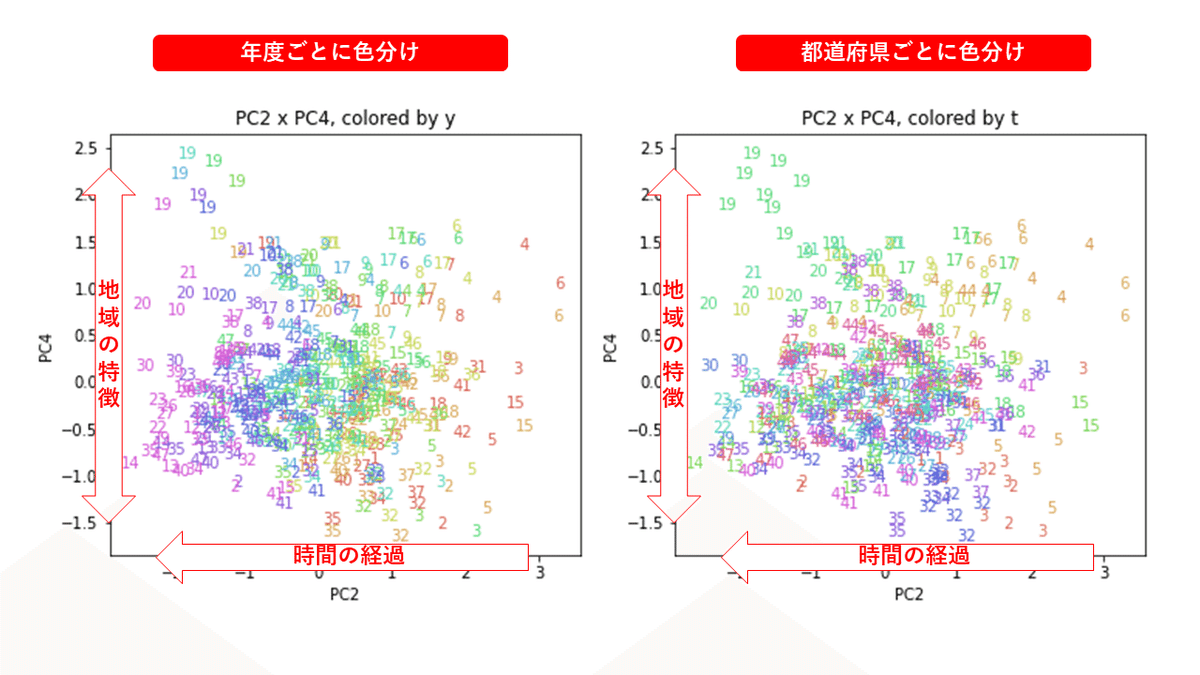

PCAの結果の第n主成分をPCnと表記します。

医療費データの場合と同様に、PCAの結果を見やすく表示するため、seabornのカラーパレットを使って、年月別、都道府県別に色分けして図示してみます(左側が年月別に色分け、右側が都道府県別に色分け)。PC1~PC8まで表示しました。

都道府県番号の表示

上の色分けだけでは都道府県が区別しにくいので、医療費データの場合と同様に、点の代わりに都道府県番号をプロットした図も描いておきます(色分けは上と同じ)。

医療費データの場合ほどはっきりとはしていませんが、PC2が概ね時間の経過を表す成分で、残りの成分が時点によって変わらない地域の特徴を表す成分となっているようです。

また、PC1×PC3を見ると、47沖縄が他の都道府県からかなり離れたところに位置しており、沖縄の地域差が際立っているのが分かります。これは、以前別の記事で年齢階級のない健診データでPCAを実行した場合と似た結果となっています。

今回は、医療費データと同様に、健診データ240次元についてPCAを実行してみました。PCAの結果、医療費データの場合ほどはっきりしとはしていませんが、第2主成分が概ね時間の経過を表す成分で、時間軸に沿った全体的な動き(全国的な動き)を表しており、それ以外の成分が地域の特徴を表す成分で、この10年間あまり変わっていないことがわかりました。